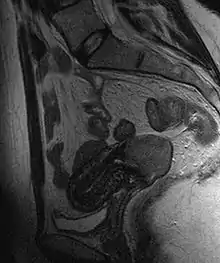

Often before the biopsy, the doctor asks for medical imaging to rule out other causes of woman's symptoms. Imaging modalities such as ultrasound, CT scan, and MRI have been used to look for alternating disease, spread of the tumor, and effect on adjacent structures. Typically, they appear as heterogeneous mass on the cervix.[53]

Staging

Cervical cancer is staged by the FIGO system, which is based on clinical examination rather than surgical findings. Prior to the 2018 revisions to FIGO staging, the system allowed only these diagnostic tests to be used in determining the stage: palpation, inspection, colposcopy, endocervical curettage, hysteroscopy, cystoscopy, proctoscopy, intravenous urography, and X-ray examination of the lungs and skeleton, and cervical conization. However, the current system allows use of any imaging or pathological methods for staging.[68]

Stage 1A cervical cancer

Stage 1B cervical cancer

Stage 2A cervical cancer

Stage 2B cervical cancer

Stage 3B cervical cancer

Stage 4A cervical cancer

Stage 4B cervical cancer